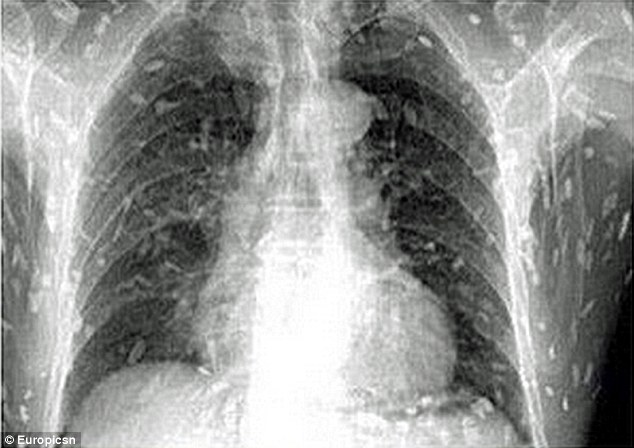

Η αγάπη ενός κινέζου – και όχι γιαπωνέζου – για το sashimi παραλίγο να του κοστίσει την ζωή. Το σώμα του γέμισε παράσιτα και αυτό απεικονίστηκε με σοκαριστικό τρόπο στις ακτινογραφίες που έβγαλε.

Ο κινέζος πήγε στον γιατρό του παραπονούμενος για πόνο στο στομάχι και φαγούρα. Ο γιατρός αποφάσισε να του βγάλει ακτινογραφίες και τότε και οι δυο έμειναν με το στόμα ανοικτό.

Όλο του το σώμα εσωτερικά ήταν γεμάτο παράσιτα. Και αυτό γιατί έτρωγε ακατάπαυστα sashimi! Οι γιατροί πιστεύουν ότι το ωμό ψάρι που έφαγε πρέπει να ήταν μολυσμένο.

Η εισαγωγή του στο νοσοκομείο ήταν άμεση. Η μόλυνση ήταν μεγάλη και μάλλον προήλθε από ωμό σολωμό.